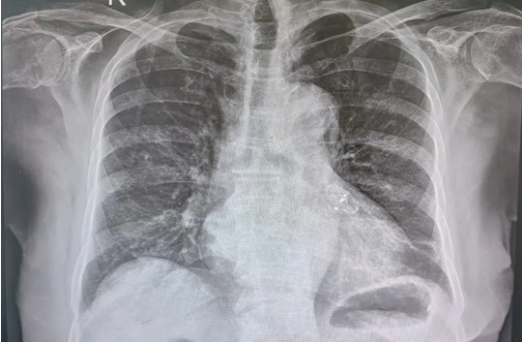

图片

术后影像片